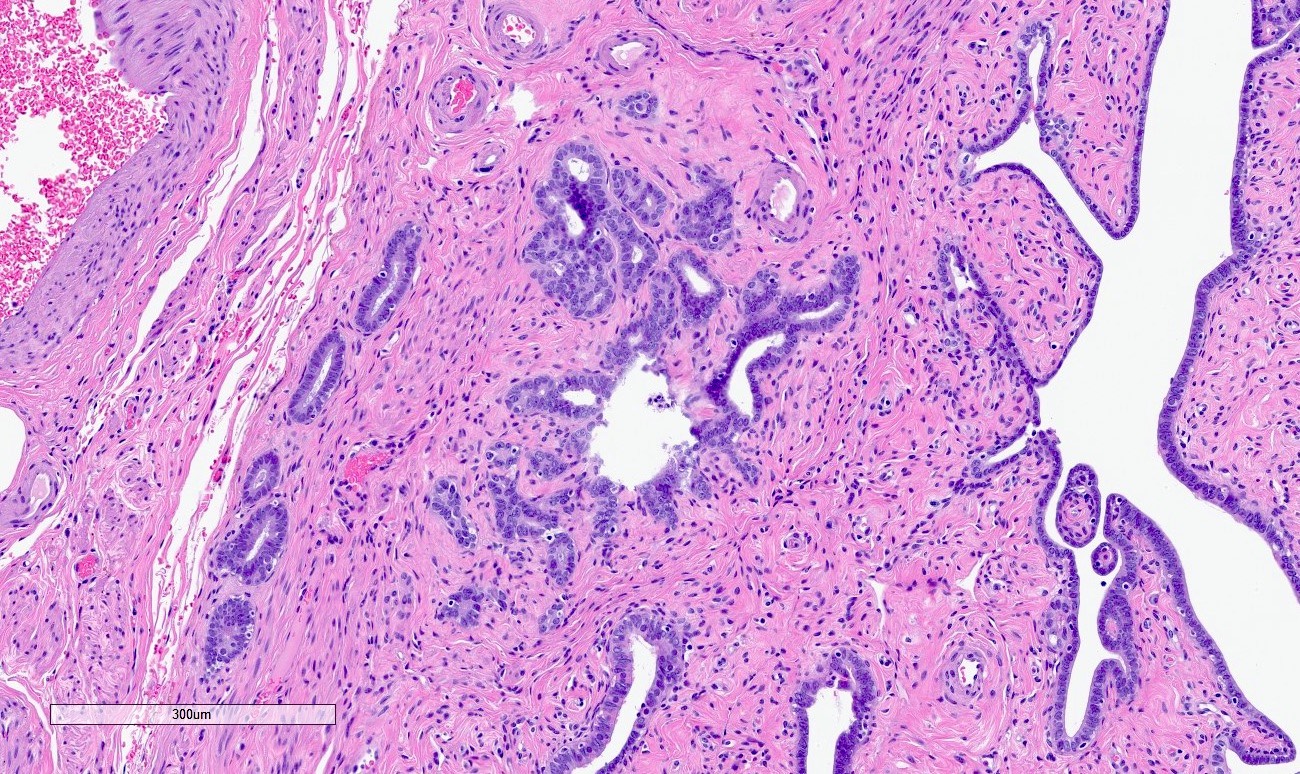

Microscopic (histologic) description

- Regularly spaced glands lined by normal appearing tubal epithelium surrounded by smooth muscle or fibrous tissue

- Tubal lumina are true diverticula that communicate with the central tubal lumen but do not connect with the serosa

- Glands can become cystically dilated (Am J Clin Pathol 1951;21:212)

- No significant atypia, scarring or associated inflammatory / stromal response

- Absence of endometrial stroma differentiates this entity from tubal endometriosis

Microscopic (histologic) images

Differential diagnosis

- Endometriosis:

- Glands are surrounded by endometrial stroma with or without hemosiderin laden macrophages

- Adenocarcinoma:

- Desmoplastic or inflammatory response and prominent cytologic atypia

- Adenomatoid tumor:

- Slit-like glands with thin, tapered septa lined by bland flattened to cuboidal cells